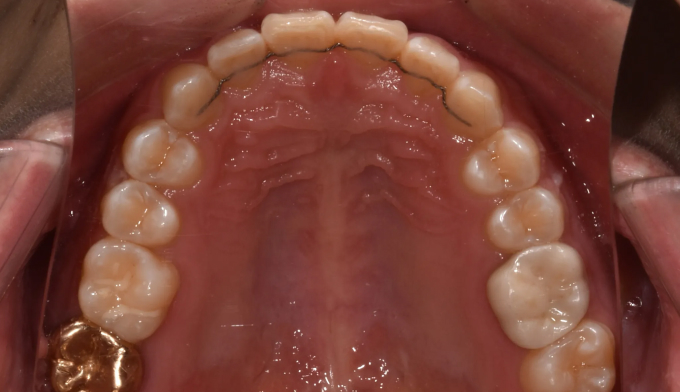

과개교합

과개교합은 앞니를 잇몸안으로 집어넣거나 반대로 어금니를 잇몸밖으로 빼내어 치료하는 방법이 있습니다.

환자의 안모 형태와 입술 두께등을 종합적으로 고려하여 치료방법을 결정합니다.

본 케이스에서는 치아 노출도를 고려하여 윗니를 위로, 아랫니를 아래로 함입하여 과개교합을 치료하였습니다.

교정기간은 총 10개월입니다.